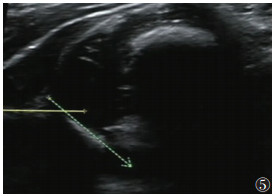

2.220例CMT合并DDH中,左侧DDH 8例,右侧DDH 6例,双侧DDH 6例。20例40髋中,Ⅰ型14髋(35.0%)(图 1)、Ⅱa型17髋(42.5%)(图 2)、Ⅱb型5髋(12.5%)(图 3)、Ⅱc型1髋(2.5%)(图 4)、Ⅲ型2髋(5.0%)(图 5)、Ⅳ型1髋(2.5%)(图 6)。

| 图 5 男,48 d,左髋α=40°,β无法测量,GrafⅢ型,骨顶缘扁平,股骨头脱位,软骨顶向上翻转 |

目前,超声已被认为是诊断CMT和DDH最敏感的工具之一,并被广泛用于两者的诊断[2, 13]。一方面,超声可用于量化CMT患儿肌肉纤维化程度,确定肿块的大小和位置,并指导临床制订治疗方案[17]。本组非肿块型98例,肿块型78例。非肿块型常仅表现为头歪向一侧,此时运用超声测量双侧的SCM的厚度、对比是否有局限性增厚,观察肌纤维排列、肌纹理回声及与周围组织关系从而早期诊断CMT;对于肿块型,超声可明确肿块来源,排除淋巴管瘤、淋巴结等其他颈部肿块。根据患侧SCM的声像图特点推测肌肉纤维化程度,从而选择治疗措施,并通过超声计算出SCM挛缩长度、确定临床手术方案和松解范围[1, 18-21]。此外,超声在后期疗效观察和判断预后上也有重要价值,通过测量治疗前后SCM厚度、肿块大小,以及观察病变区血流情况,有利于评估CMT疗效。另一方面,相对于体格检查较明显的CMT,DDH可能更易忽视;尤其6个月以内的婴幼儿,因髋臼软骨未骨化X线不能显像,早期诊断DDH更困难。而超声波可穿透软骨,清晰显示关节囊、关节盂唇、股骨头软骨及髋臼等解剖结构;其中Graf超声静态测量方法因敏感性高,且观察者间的图像采集测量解读差异小、可重复性较高等优点,能更早期发现DDH,在婴儿髋关节超声检查中最普及[16, 22-23]。本组176例CMT患儿,通过Graf方法对髋关节进行分型,显示并发DDH 20例(40髋),其中Ⅰ型14髋(35.0%)、Ⅱa型17髋(42.5%)、Ⅱb型5髋(12.5%)、Ⅱc型1髋(2.5%)、Ⅲ型2髋(5.0%)、Ⅳ型1髋(2.5%),临床上根据具体病理阶段选择和实施合适的治疗,病情均得到不同程度的改善、获得满意的治疗效果。此外,应用彩色多普勒超声还可监测DDH治疗过程中股骨头血供情况,以减少股骨头坏死的发生[24]。